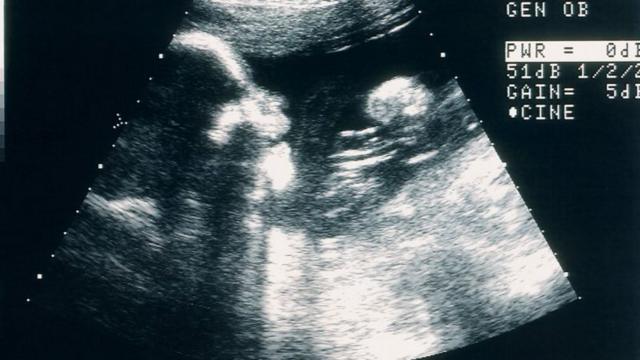

“Tinha ido ao médico por outro problema e quando contei que estava grávida fizeram uma ultrassonografia. Quando não encontraram batimento cardíaco, foi um choque emocional pra mim. Não havia tido problemas, não tinha nenhum indíciobet pix comque algo estava errado”, diz ela.